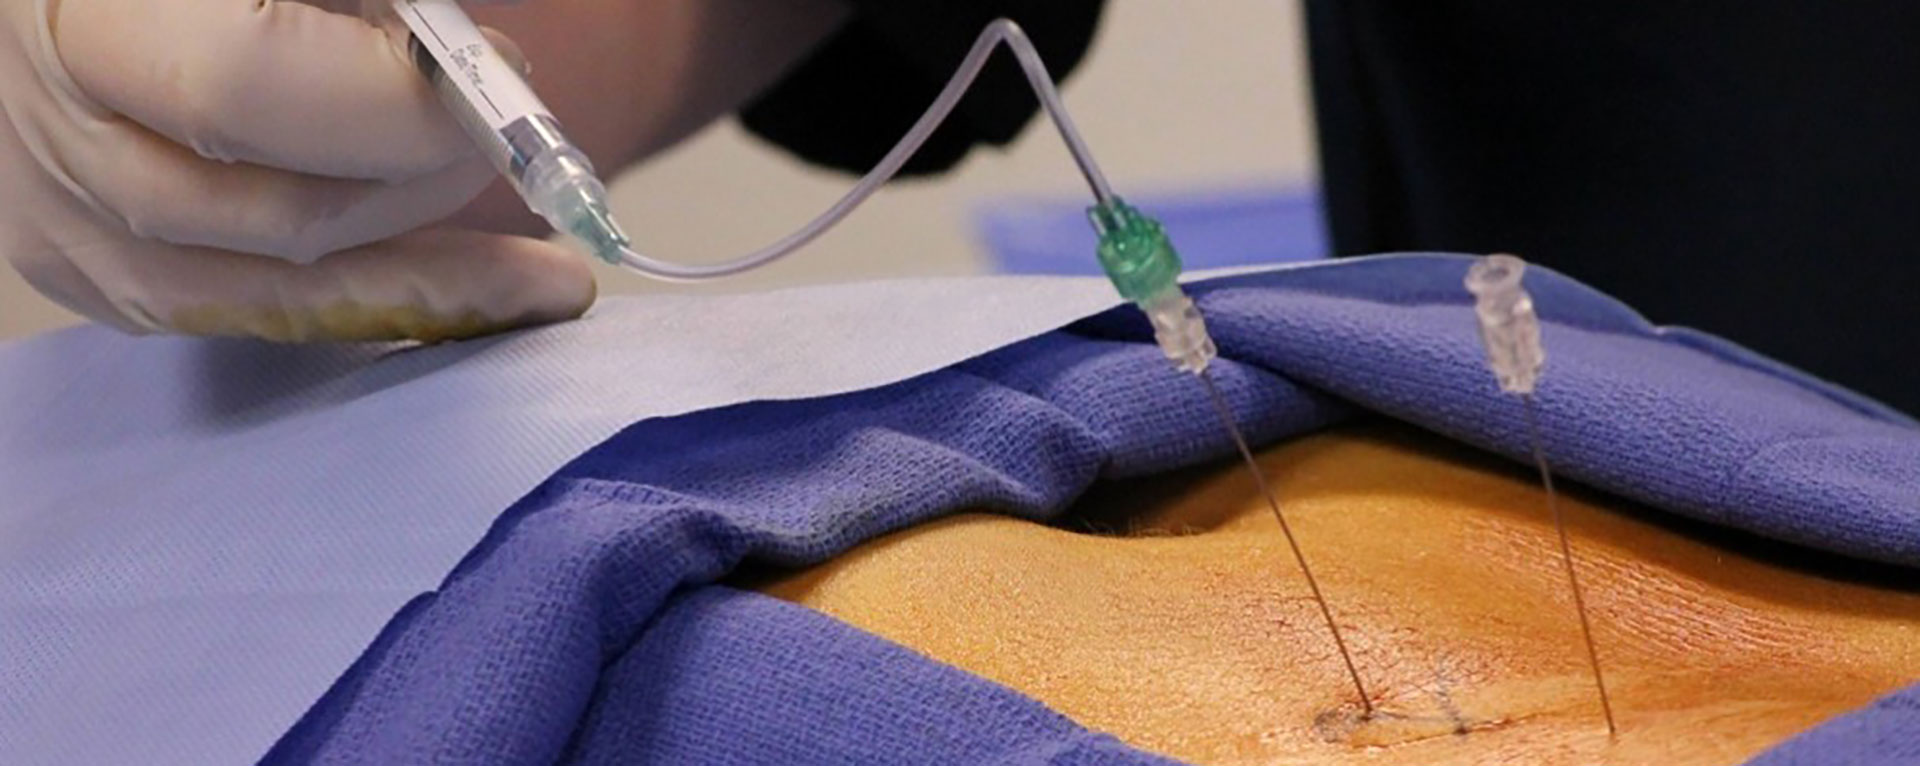

مطب دکتر زارعی با محوریت کنترل و درمان دردهای حاد و مزمن از سال ۱۳۹۷ در خدمت بیماران محترم می باشد.

مشاوره بیهوشی، مراقبتهای ویژه و آی سی یو، مدیریت و درمان دردهای حاد و مزمن نظیر دردهای نوروپاتیک، دردهای مفصلی، دردهای ستون فقرات (گردن و کمر) و آرتروز مثالهایی از فعالیتهای تخصصی دکتر زارعی هستند. ایشان همچنین آماده پاسخگویی و مشاوره در زمینه کنترل درد در بیماران سرطانی و دردهای رایج پس از ترک اعتیاد می باشند.